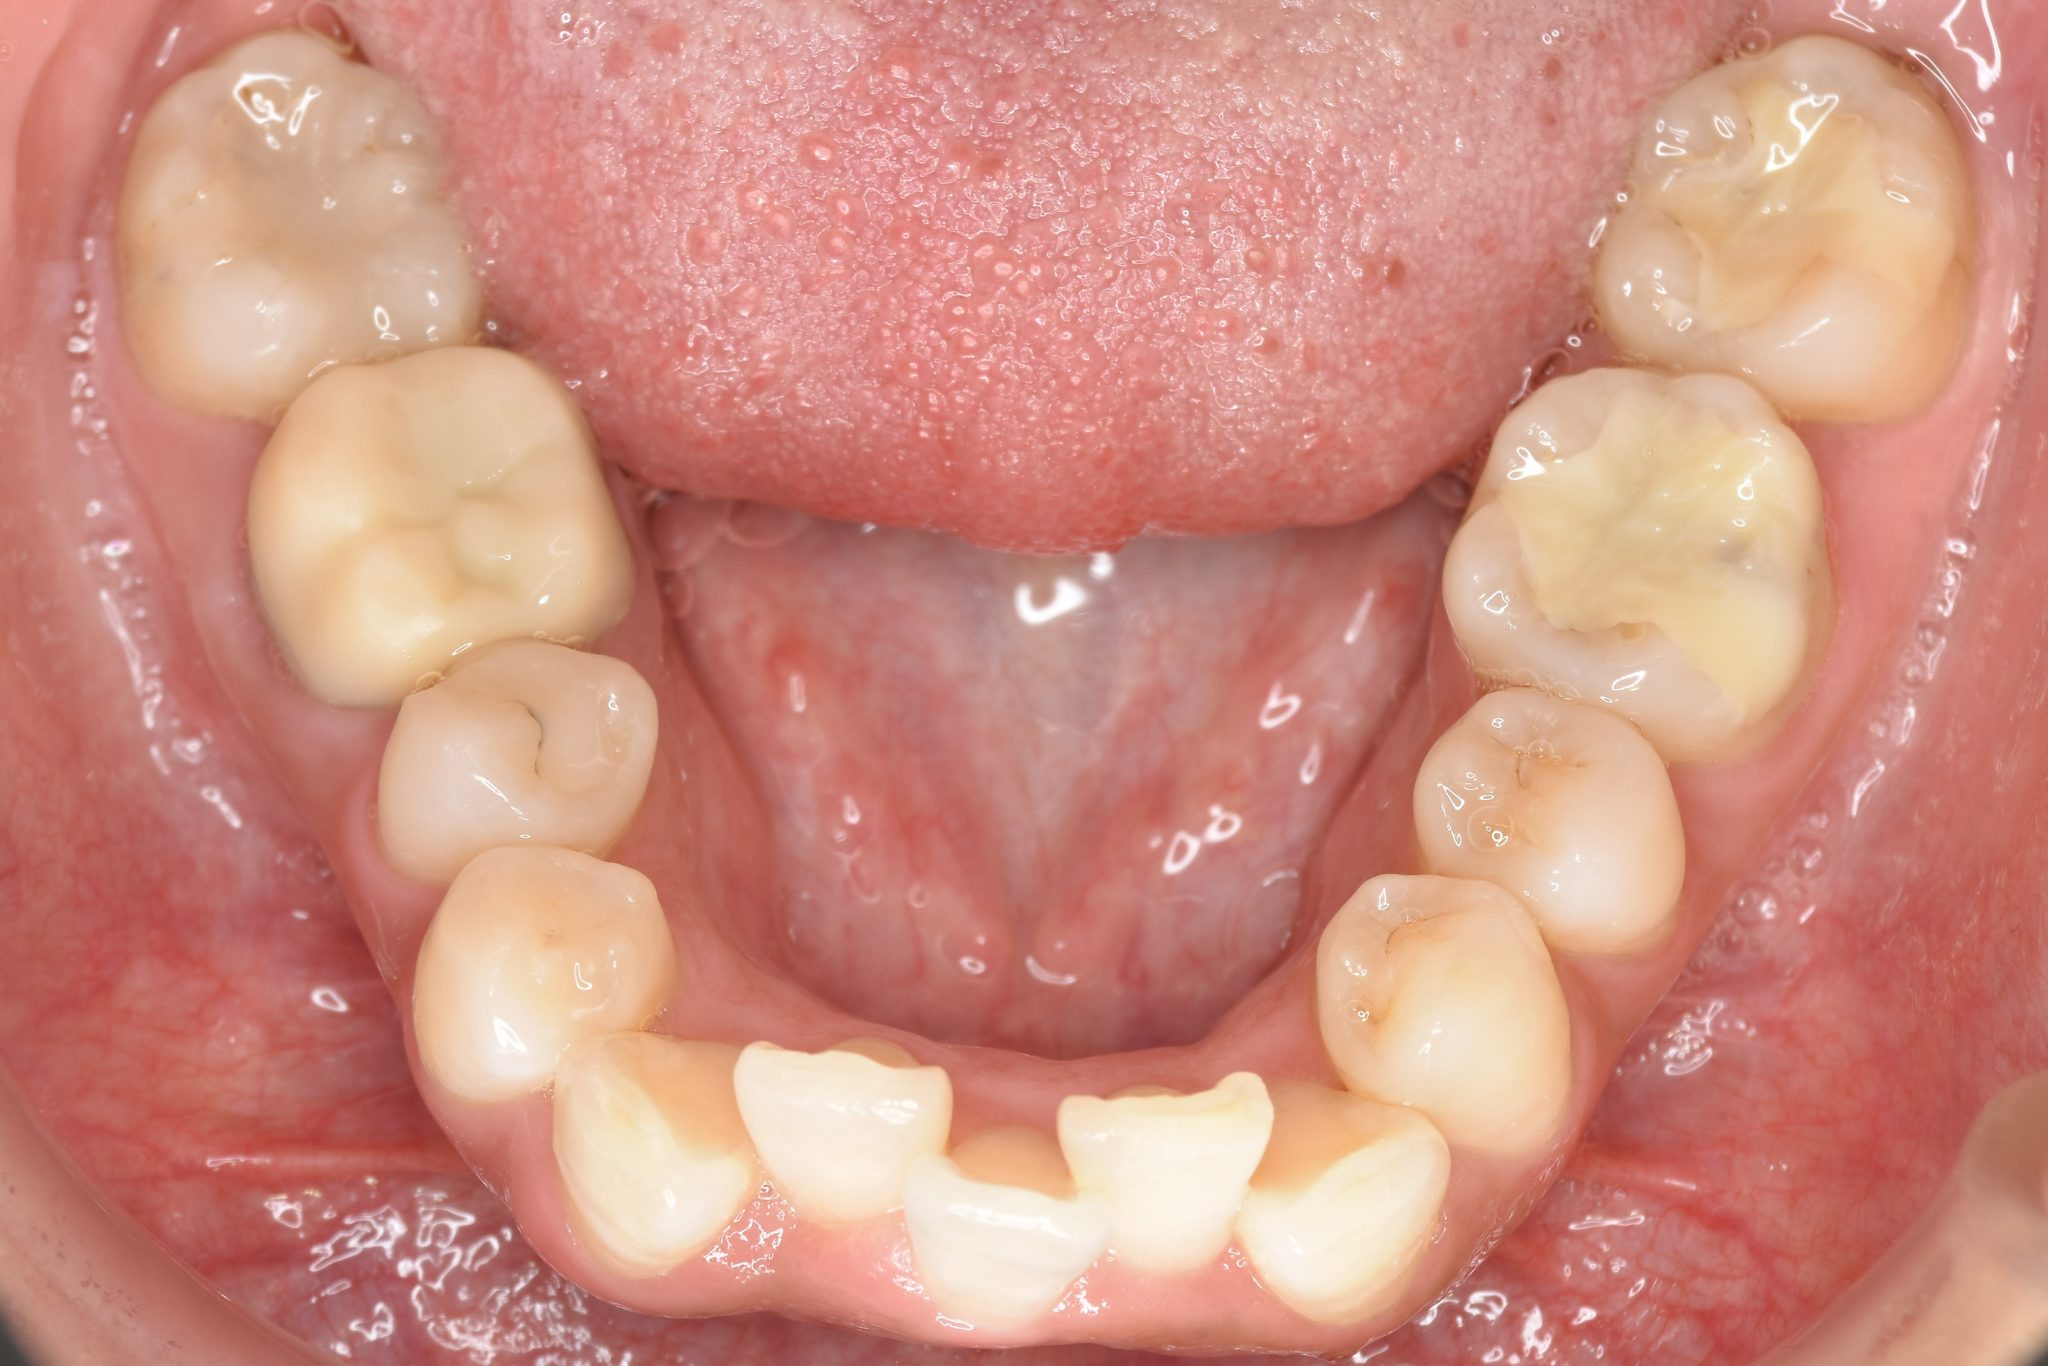

ビフォー

インビザライン矯正治療|症例_649